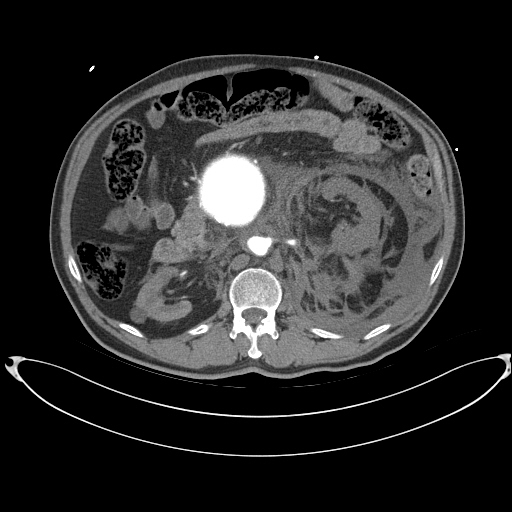

- CT(컴퓨터단층촬영) – X선을 사용하며, 조영제 사용 시 드물게 알레르기나 신장 기능 저하 가능성이 있으므로 검사 후 24시간은 충분한 수분을 섭취하는 것이 좋습니다.